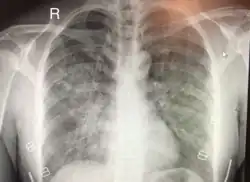

| Chest x-ray of HAPE showing characteristic patchy alveolar infiltrates with right middle lobe predominance. | |

Hypoxic pulmonary vasoconstriction (HPV) occurs diffusely, leading to arterial vasoconstriction in all areas of the lung. This is evidenced by the appearance of "diffuse," "fluffy," and "patchy" infiltrates described on imaging studies of climbers with known HAPE.[9]

On physical exam, increased breathing rates, increased heart rates, and a low-grade fever 38.5o C (101.3o F) are common.[9][3] Listening to the lungs may reveal crackles in one or both lungs, often starting in the right middle lobe.[9][3] Imaging studies such as X-ray and CT imaging of the chest may reveal thoracic infiltrates that can be seen as opaque patches.[14][9][3] One distinct feature of HAPE is that pulse oximetry saturation levels (SpO2) are often decreased from what would be expected for the altitude. People typically do not appear as ill as SpO2 and chest X-ray films would suggest.[9][3] Giving extra oxygen rapidly improves symptoms and SpO2 values; in the setting of infiltrative changes on chest X-ray, this is nearly pathognomonic for HAPE.[3]